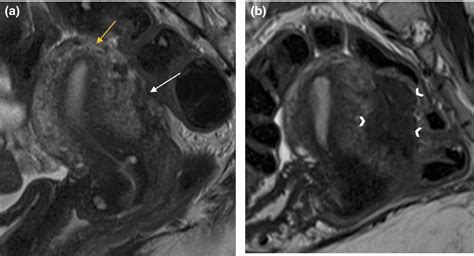

Diagnosing conditions affecting the Posterior Cul De Sac often involves a combination of medical history, physical examination, and diagnostic tests. Some of the most common diagnostic techniques include:

• MRI: An MRI uses magnetic fields and radio waves to create detailed images of the body's internal structures. This test can provide valuable information about the Posterior Cul De Sac and surrounding tissues.

• Advanced Imaging Techniques: New imaging technologies, such as high-resolution MRI and CT scans, are being developed to provide more detailed and accurate images of the Posterior Cul De Sac and surrounding tissues.